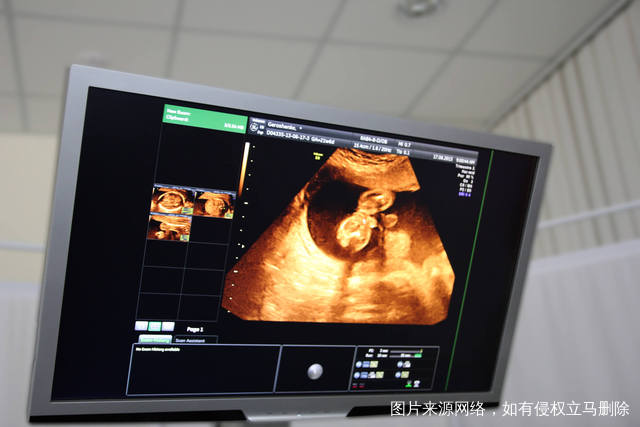

近几年,不孕不育人群并没有减少,反而在增加,主要是由于现在生育年龄普遍增大、过早进行人工流产、饮食环境差、不良生活习惯、先天性疾病等。多种多样的不孕也加大了治疗难度,一些夫妻经过了多年的治疗依然不能怀孕,这样的情况下可以考虑做试管婴儿的,对于试管婴儿很多人通过科普资料已经有了一些了解,但是对于细节了解还是很少,最近有患者提出这样的问题:试管婴儿是冷冻卵子还是受精卵呢?必须冷冻吗?今天就这个疑问我们来做个简单的介绍。